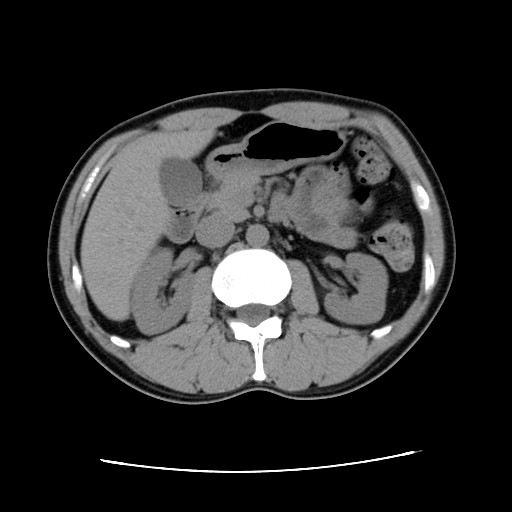

ちなみにこっちは1年半前の2010/5/27です。

腹回りの脂肪に著変なしw。